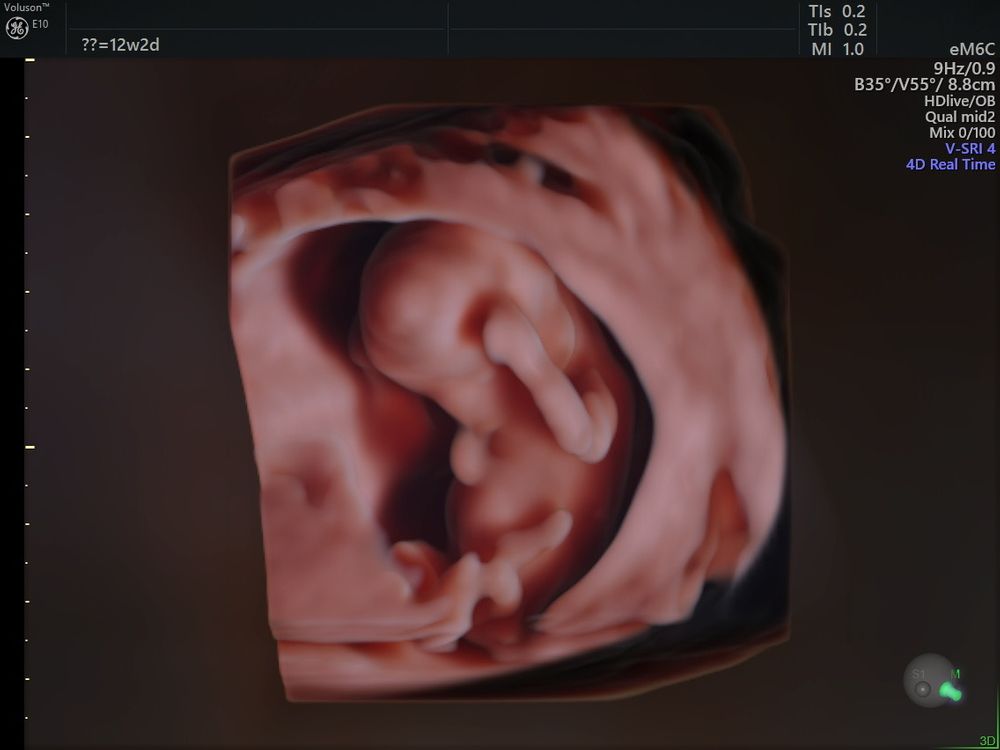

Дорогие мои читательницы, доев свой сочный сырник я начинаю свой пост о том, как мы уже 12 недель и 2 дня вместе и я только пришла с первого в своей жизни скрининга 😍🤭

Ну собственно человек вырос, лежал говорил по телефону 🤣😂(фото прилагается) и икал, а так очень спокойный, даже кофе его не взбодрил)

Риски минимальные, сердечко чистое)

Плацента низко, но говорят поднимется еще, как бывает в 90% случаев. Я за ЕР, поэтому конечно надеюсь на благоприятные условия.